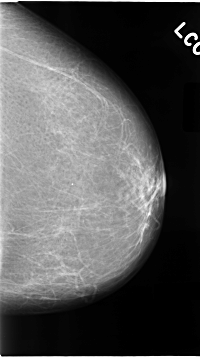

C_0073_1.LEFT_MLO

LEFT_MLO LINES 4672 PIXELS_PER_LINE 2848 BITS_PER_PIXEL 12 RESOLUTION 50 NON_OVERLAY